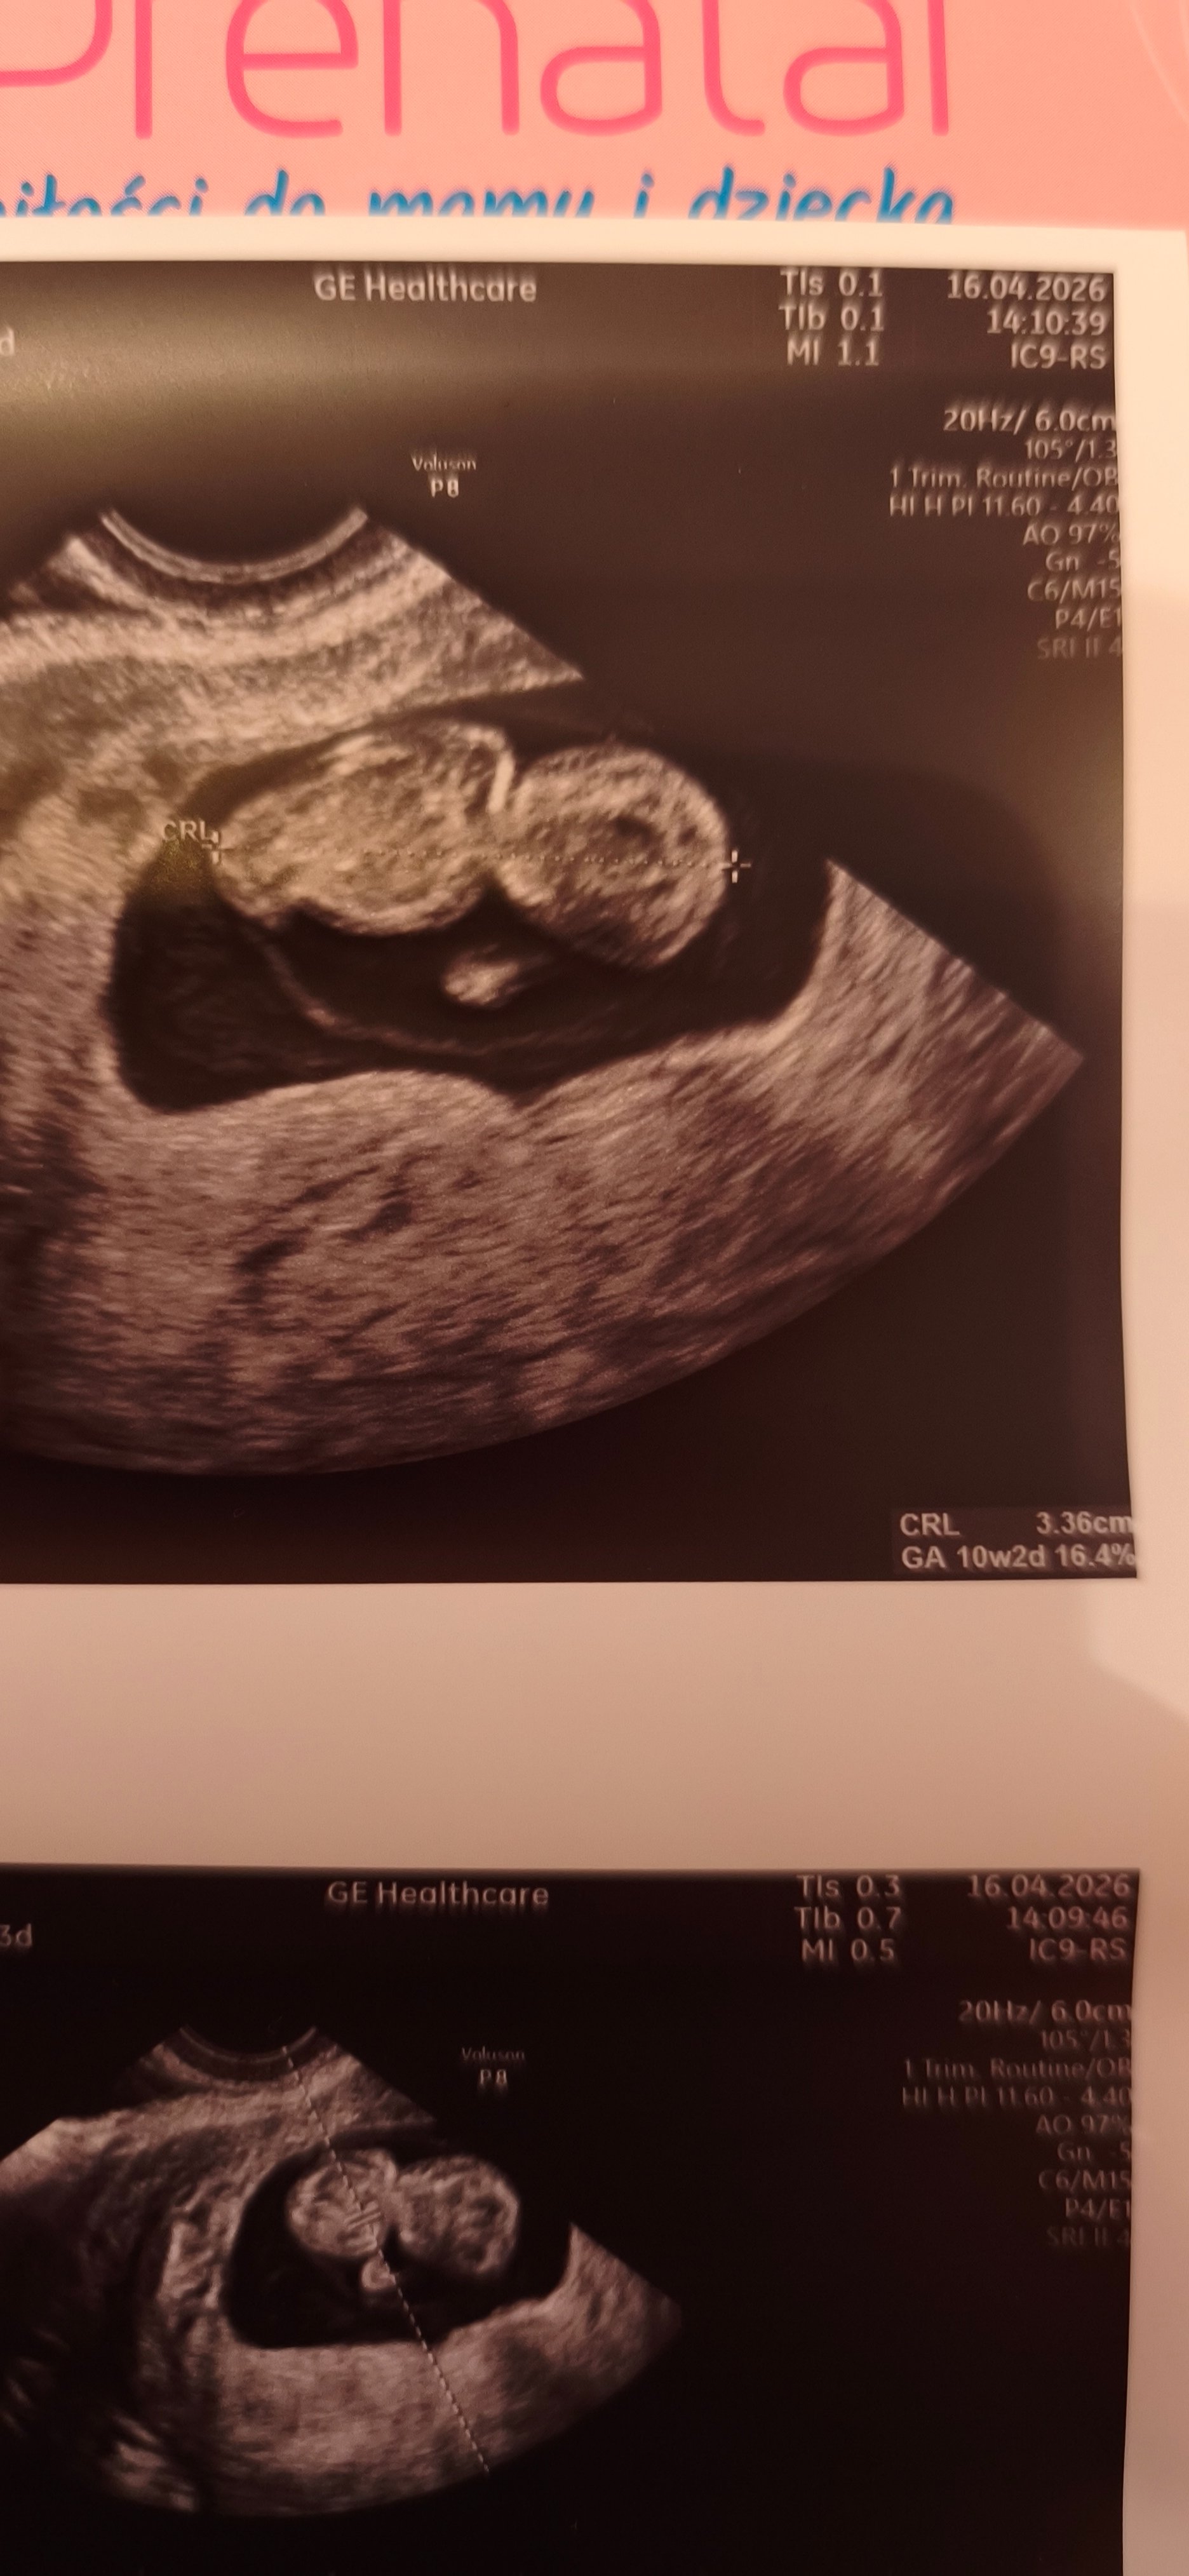

• IMG20260413152404.jpg

IMG20260413152404.jpg

1,4 MB · Wyświetleń: 40

• IMG20260413152401.jpg

IMG20260413152401.jpg

815,6 KB · Wyświetleń: 40